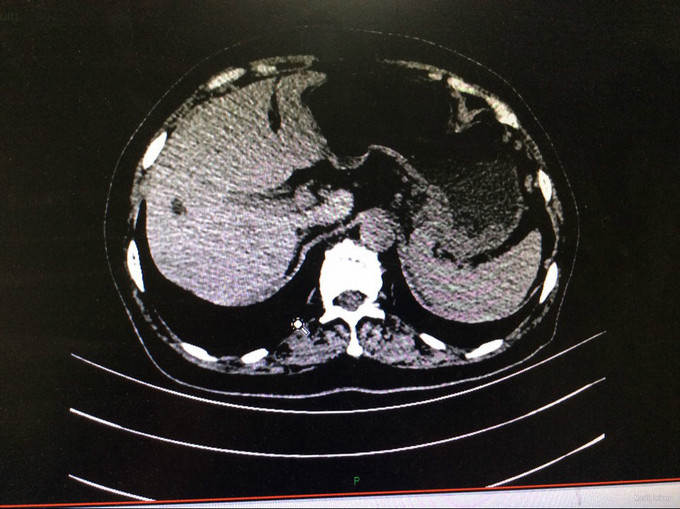

查体:生命体征平稳。神智清,查体合作,面容正常,淋巴结未触及肿大。双肺听诊呈清音,为闻及干湿罗音及哮鸣音;心率78次/分,律齐,无异常心音及心脏杂音;腹平软,肝脾肋下未及,未触及肿块,无压痛及反跳痛,肠鸣音正常。双下肢无水肿,生理反射存在,病理反射未引出。专科查体:无明显异常。辅助检查:湖北省中医院CT示:胰腺占位。CT检查示:1.结合原CT、MR检查,胰腺体尾部及周围异常改变,考虑胰腺炎伴坏死囊性变可能性大,与2015-11-20CT相比较,囊性病变略缩小;腹膜后淋巴结增多增大,大致同前;2. 所及肝脏多发囊肿;肝右叶后段其中一个病变边缘可疑强化,大小与前次相仿;3. 左侧肾上腺饱满。 MRI检查示: 胰腺体尾部及周围异常改变,考虑胰腺炎伴坏死囊性变可能性大,合并肿瘤性病变待排,病变累及腹膜伴腹膜后淋巴结增多增大,腹腔少许积液,请结合检查结果考虑;2. 所及肝脏多发囊肿;肝右叶后段其中一个病变边缘可疑强化,需鉴别于血管瘤与转移性病变,建议随访复查;3. 左侧肾上腺饱满;4. 所及右侧胸廓外小结节(层面16-7),直径约4mm,不除外右乳的病变:5. 所及腰椎骨性纵裂畸形。病理检查:(胰体尾部肿块穿刺组织)高分化腺癌,考虑为IPMN相关性浸润性癌。